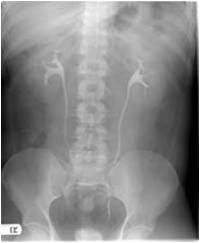

Radiograph #1

Urinary Tract

Identify: Minor calyx, major calyx, renal pelvis, ureter, left kidney, right kidney, ala sacrum.